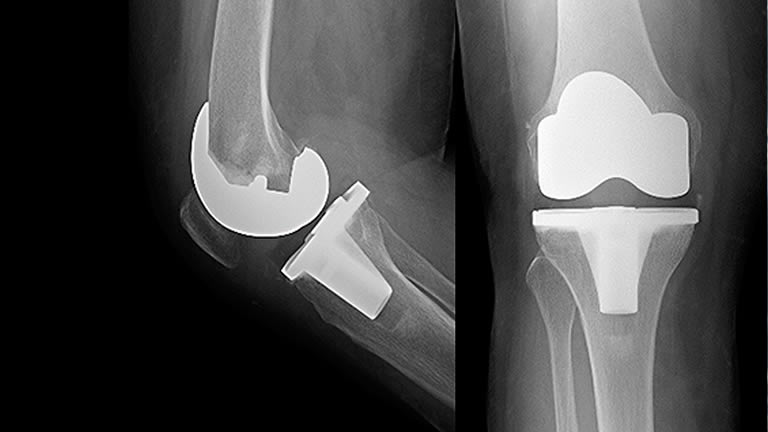

The ends of the knee joint are encased in metal components, and a medical-grade plastic implant is used to create the new cushion in the knee. It is the patient's own muscles and ligaments that provide the strength and stability to their new knee.